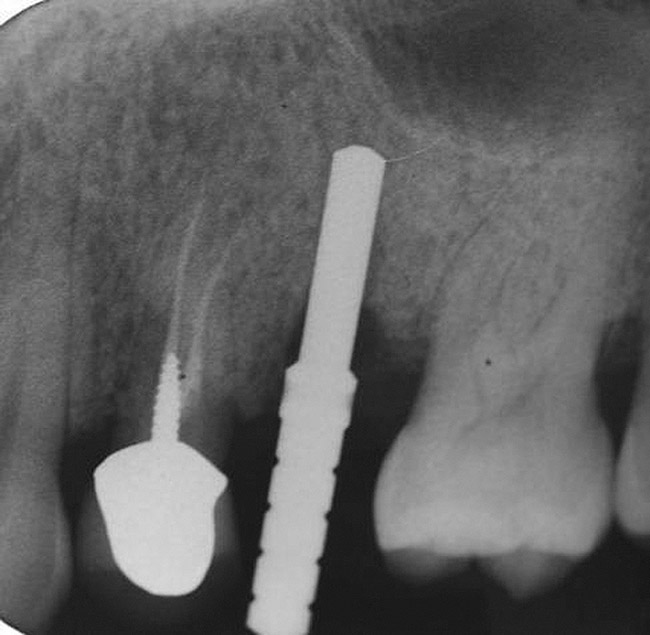

With a 2-mm twist drill in the handpiece, the head of this tool is aimed at the opposite jaw to attain the proper angulation for drilling the osteotomy. The initial development of the osteotomy with the 2-mm drill should be done to a depth of approximately 5 mm, and then a guide pin should be placed to assess osteotomy angulation (Figure 8).29 At this juncture, alterations in angulation can be done with the twist drill. Also, guide pins can be placed into multiple osteotomies to assess parallelism between implants and/or adjacent structures. At this early stage, parallelism should be adjusted as necessary.

When a 2-mm twist drill is used to full depth of the osteotomy (eg, 10 mm), it is difficult to change osteotomy angulation with a twist drill. If a correction is necessary, a side-cutting bur (eg, Lindemann) should be used (Figure 9). Furthermore, if there are doubts as to closeness of the osteotomy to adjacent teeth or vital structures, then a radiograph with a guide pin in place should be obtained.30 Ultimately, the angulation and location of the osteotomy should be consistent with design of the future restoration.31